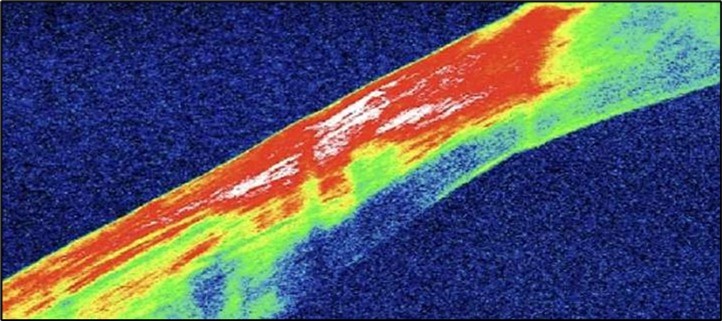

Serial anterior segment OCT was employed throughout treatment to monitor corneal changes and response to interventions. Figure 7a, Figure 7b, Figure 7c, Figure 7d illustrate the ulcer’s progression: initial severity, minimal early response to medical therapy, post-operative healing after conjunctival resection, and sustained recovery at six-month follow-up.

Figure 7c.(1-month post conjunctival resection): There is evidence of stromal remodeling with near-complete epithelial regeneration. The ulcer margins appear smoother, and stromal reflectivity is reduced, indicating diminished inflammation. The transition between the ulcerated and normal cornea is more gradual, consistent with active healing and fibrotic repair.

Figure 7d.(6 months follow-up): OCT demonstrates complete structural restoration of the cornea with a smooth anterior contour, full re-epithelialization, and resolution of the ulcer defect. Mild residual stromal hyperreflectivity remains, consistent with fibrotic scarring. There is no evidence of epithelial breakdown or recurrence, indicative of a quiescent disease state